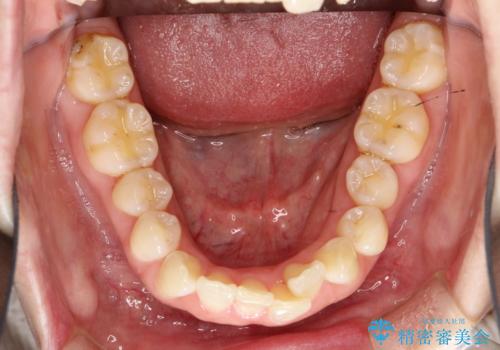

【モニター】処置歯の多い歯列 インビザラインでデコボコを整える